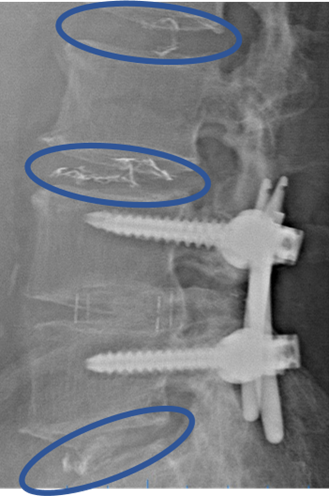

L4/5: 固定術後

DiscoGelを入れた後の画像になります。

治療は 40分程度で終了

回復室で休憩後、歩いて帰院されました。